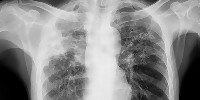

Д-р Бацелова: Заболяването започва с висока температура и отпадналост, характерно зачервяване на очите и обрив по цялото тяло

Случаите на морбили във Врачанско се увеличават. Вече са регистрирани 17 случая - повечето при неваксинирани деца. Има…

Доц. Атанас Мангъров: Няма предпоставки за паника за епидемия от морбили, но реална опасност има

За момента няма място за паника, но опасността е напълно реална. Защото това е заболяване, което го има,…